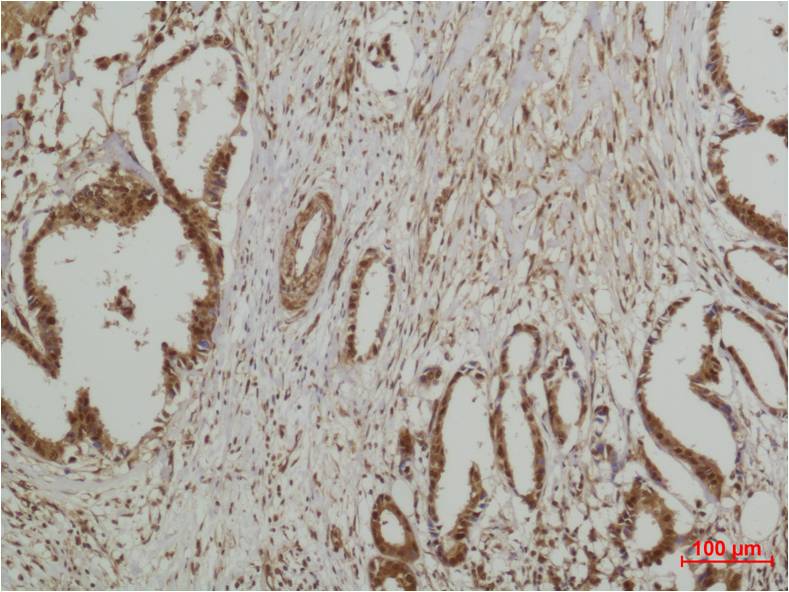

Product name: ERK5 Rabbit pAb

Dilutions: WB 1:1,000-2,000?? IHC 1:200-500

Background: ERK5, Mitogen-activated protein kinase 7 also known as MAP kinase 7 is an enzyme that in humans is encoded by the MAPK7 gene. MAPK7 is a member of the MAP kinase family. MAP kinases act as an integration point for multiple biochemical signals, and are involved in a wide variety of cellular processes such as proliferation, differentiation, transcription regulation and development.